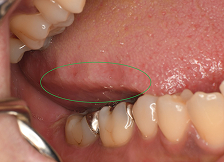

8舌の側面や頬の内側に噛みこみの跡がある

噛みこみの跡がある

9歯と歯ぐきの境目にえぐれたような凹みがある 歯磨きの時に歯がしみる

歯がしみる